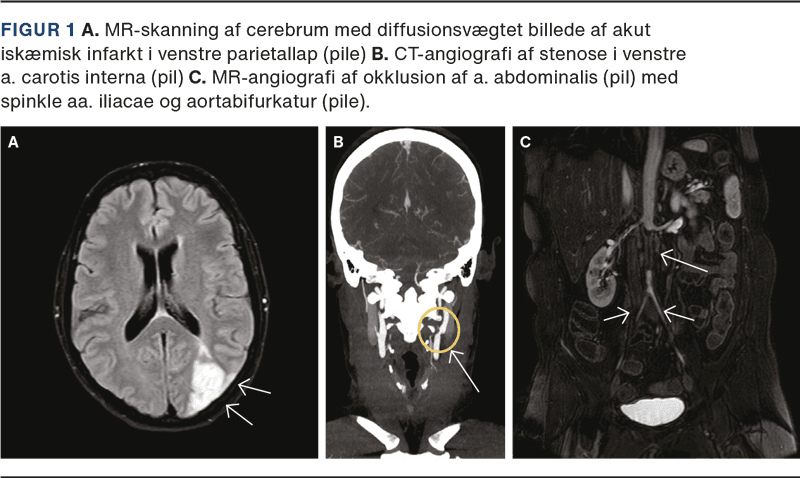

En 44-årig kvinde med Sjögrens syndrom og mangeårig fibromyalgi blev indlagt grundet hovedpine varende tre uger og ordmobiliseringsbesvær varende en uge, ændret finmotorik i højre hånd samt fokuserings- og forståelsesvanskeligheder ved skrivning og læsning. En neurologisk undersøgelse viste herudover højresidig øvre homonym kvadrantanopsi og visuel inattention mod højre. MR-skanning af cerebrum viste subakutte infarkter i venstre vandskelsområder, og CT-angiografi af hjerne og halskar viste svære stenoser proksimalt i venstre a. carotis interna, a. carotis externa og a. subclavia (Figur 1 A + B).

Patienten klagede over smerter i venstre arm med forværring ved brug og havde gennem syv år haft tiltagende smerter i begge ben med forværring ved gang. Ved indlæggelsen kunne hun gå 50 meter med rollator, men var primært mobiliseret i kørestol. Det seneste år oplevede hun ved gang tab af følesans fra navlen og nedefter samt tab af kontrol over defækation og vandladning. CT-og MR-angiografi viste okklusion af aorta abdominalis infrarenalt med genåbning ved bifurkaturen og spinkle aa. iliacae (Figur 1C). MR-skanning af medulla spinalis var normal. Ved karkirurgisk vurdering fandt man manglende lyske- og fodpuls i begge ben, ankeltryk på 30-40 mmHg (normalt 10-20 mmHg højere end højeste armtryk), manglende håndledpuls venstresidigt samt blodtryk på 106/64 mmHg og 132/64 mmHg på hhv. venstre og højre arm. Patienten fik foretaget perkutan transluminal angioplastik af venstre a. subclavia og indsat en aorto-bifemoral protese. Histologisk undersøgelse af vævsprøve fra aorta viste svær cellefattig sklerose uden tegn på aktiv artritis.